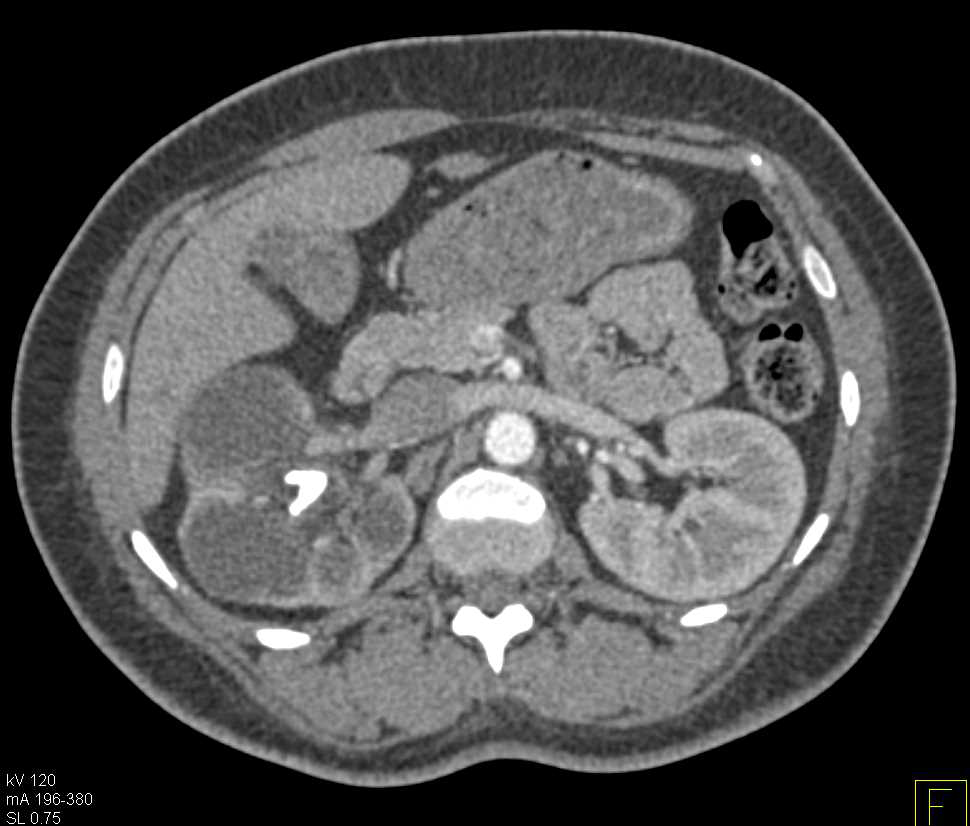

Xanthogranulomatous Pyelonephritis (XGP) Right Kidney